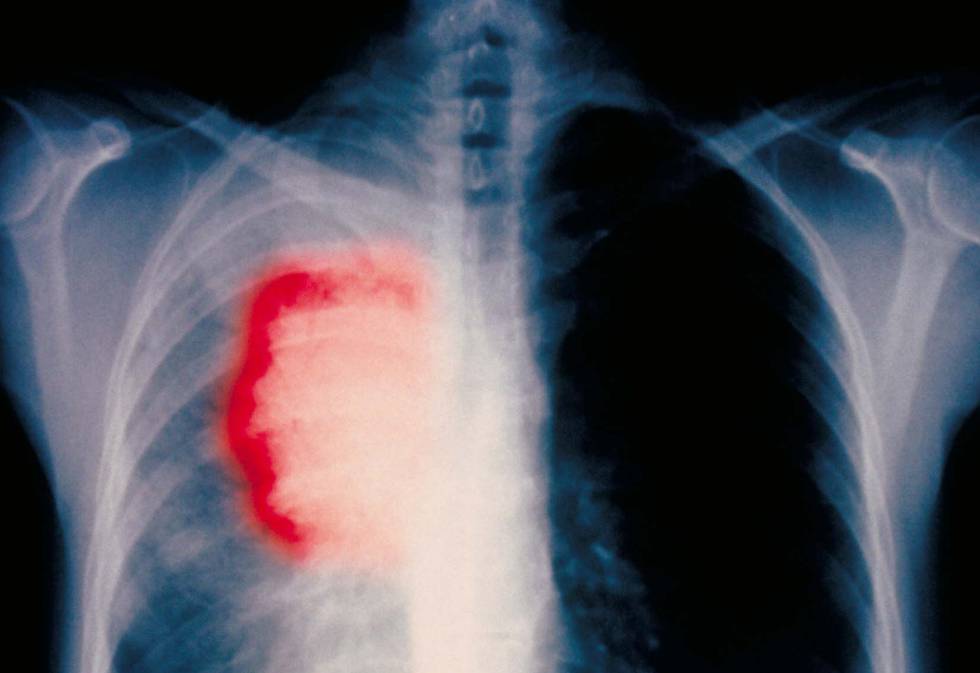

Investigadores del Grupo Español de Cáncer de Pulmón (GECP) han descubierto un nuevo tratamiento basado en quimioterapia e inmunoterapia que permite reducir el cáncer de pulmón y evitar la recaída en el 80 % de los pacientes que se encuentran en estadios intermedios de la enfermedad.

Por otro lado, este tratamiento es específico para pacientes que se encuentran en fases intermedias de la enfermedad, también conocidas como “estadio 3”, que se caracteriza por presentar diagnósticos “potencialmente curables” a través de cirugía, pero con tasas de supervivencia “muy limitadas”.